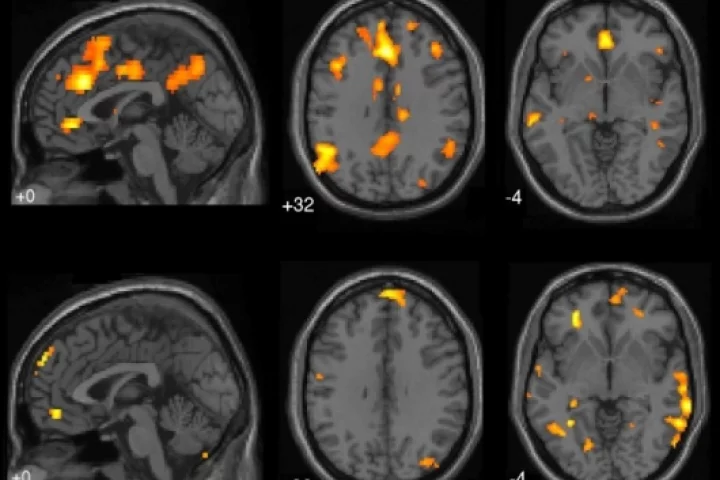

fMRI

A new study has found that specific regions of the brain are activated after a drug is taken intravenously but not when the same drug is taken orally. The findings could lead to new treatments for addiction.